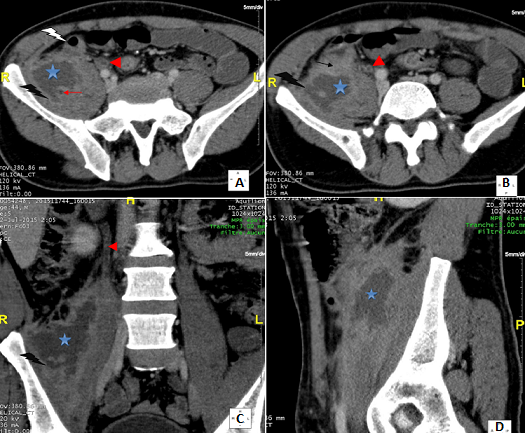

Primitif ou secondaire, l'abcès du psoas est une entité rare. Son diagnostic étiologique peut s'avérer délicat. En ce sens l'apport de l'imagerie et en particulier de la tomodensitométrie est fondamental. Malgré les examens d'imagerie, l'origine de l'abcès peut demeurer inconnue et découverte qu'en peropératoire (66% des cas). L'appendicite occupe la deuxième place (16%) après la maladie de Crohn (60%) parmi les étiologies digestives des abcès du psoas. L'appendice siège dans 26 à 65% des cas en position rétro-cæcale. Dans cette position, l'appendice peut loger dans une fossette péritonéale ou en rétropéritonéale et l'infection évoluer vers la formation d'un abcès, la diffusion vers l'espace rétropéritonéal, et rarement se compliquer d'un abcès du psoas. L'appendicite aiguë rétro-cæcale réalise un tableau clinique insidieux, atypique dans plus de la moitié des cas. A ce propos nous en rapportons une observation d'un homme de 34 ans, diabétique insulinodépendant, ayant présenté une douleur de la fosse iliaque et lombaire droite depuis une semaine. A l'examen, il était fébrile à 38,5ºC et il y avait un psoïtis, une sensibilité de l'hémi-abdomen droit, et une masse para-ombilicale et lombaire droite. Il existait une hyperleucocytose à 24000/mm3 et une CRP à 109 mg/l. La tomodensitométrie abdominale (A, B, C, D) avait montré un abcès du psoas droit d'origine appendiculaire. Par une incision de Mac Burney, l'appendice était rétro-cæcal abcédé compliqué d'un abcès du psoas. Il a été réalisé une appendicectomie, une évacuation de la collection purulente du psoas et un drainage. Sous antibiothérapie, les suites opératoires étaient simples.